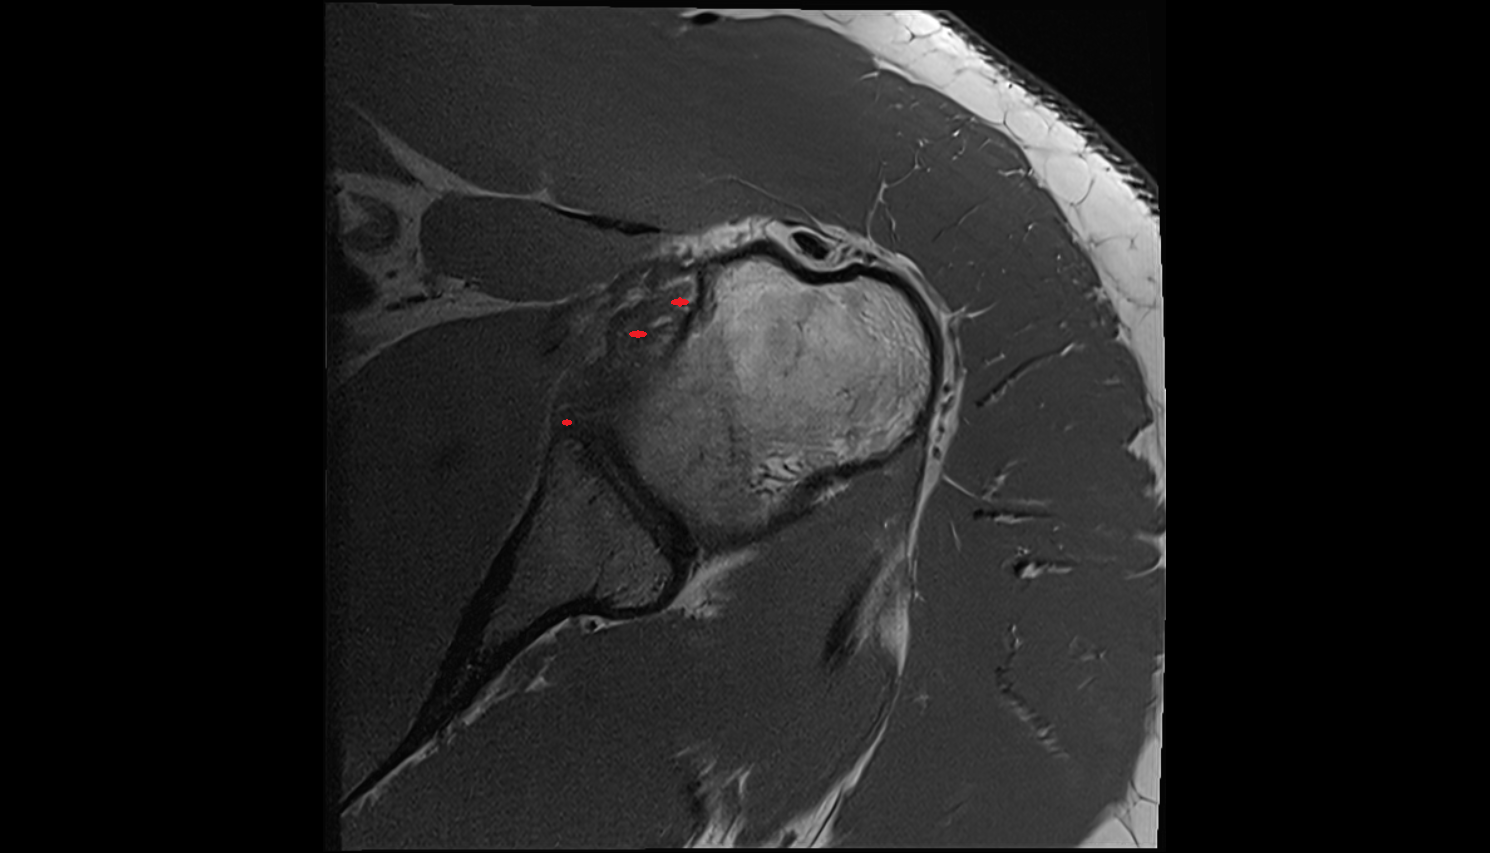

- Glenoid fossa

- Head of humerus

- Glenoid labrum

- Shoulder joint (glenohumeral joint)